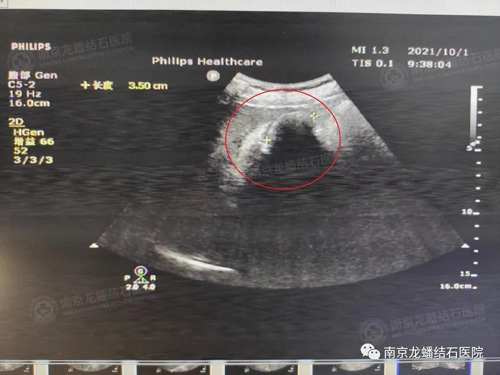

B超图

哪知道到了9月下旬的一天,韩先生右上腹部突然剧烈疼痛,像一把刀子在割似的。这下他感觉不对劲了,赶紧来到了本地的医院就医。通过检查发现,韩先生的胆囊里竟然有4个大小不等的结石,最大的一颗差不多和鸡蛋一样大小。

人体的胆囊正常情况长约60-80mm,宽约30-40mm,如同一个梨型口袋状的器官,其内部容积是在30-40ml。而韩先生这4颗结石已经掠夺了近90%的胆囊空间,由于结石长期刺激胆囊粘膜导致了急性胆囊炎,还引发了急性胰腺炎。

经过2个多小时的手术,终于成功将4枚黑褐色结石取出,较大的那个结石约3.5*3.0cm,相当于一个鸡蛋大小。